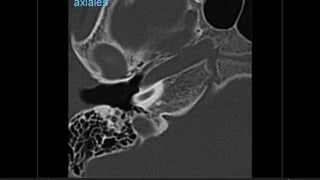

• #37 En relación ala punta del peñasco La nuieva clasificación esta en realacion a las secuelas potenciales, se demostró k hay mas secuelas

• #38 Izqu. AXIAL-- fxLongitudinal perdonan la capsula otica (laberinto oseo) Centro AXIAL fx trnasversa lascuales tperdonan el lab erinto oseo Dere: MIXTA – tmp perdona